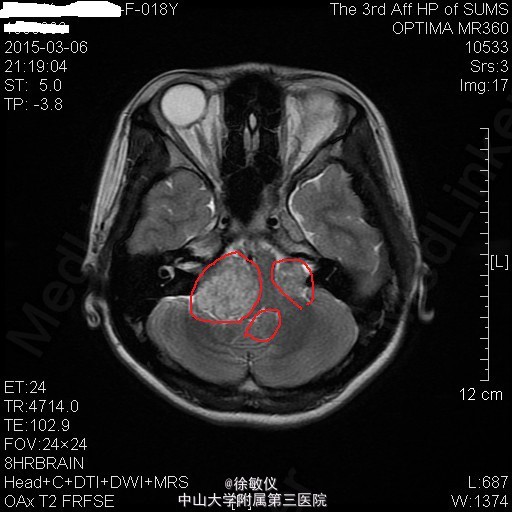

青年女性,主诉:左侧面部麻木,右侧听力下降半年。

查体:神清,查体合作,对答切题。颈软,无抵抗。左侧面部浅感觉痛觉过敏。双侧眼球运动正常,双侧视野粗测无缺损。右侧听力粗测听力下降。双侧瞳孔等大等圆,直径3mm,对光反射灵敏。双侧肢体肌力5级,肌张力正常。病理征未引出。 辅查:头颅MR提示:双侧桥小脑角区、鞍上池右侧、左侧三叉神经颅内段及枕部多发占位,考虑为神经纤维瘤病II型。

诊断:双侧听神经鞘瘤 排除手术禁忌症后,在全麻下行显微镜下经右侧乙状窦后入路右侧桥小脑角区占位病变切除术,术程顺利。术后于SICU监护治疗1天后顺利转回我科,予抗感染、脱水降颅压、营养支持及对症治疗,患者恢复良好。 术后病理诊断:(桥小脑角占位)形态结合免疫组化结果,符合神经鞘瘤。免疫组化结果(⑥):S100(+),Vim(+),Ki-67(1%+)。 术后复查头颅MR示:1、右侧听神经瘤术后改变,右侧桥小脑角区占位大部分已切除,术区少量积液同前;左侧侧脑室内少量积血,基本同前。 2、左侧桥小脑角区、鞍上池右侧、左侧三叉神经颅内段及枕部多发占位同前,考虑神经纤维瘤病。